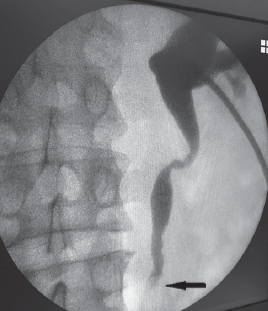

С февраля 2018 г. у пациента появились периодические боли в пояснице справа. В мае с приступом правосторонней почечной колики лечился в центральной районной больнице, где на УЗИ выявлено расширение лоханки справа до 32 мм, чашечек — до 10 мм, но после купирования колики лоханка сократилась до 19 мм. Больной снова консультирован онкоурологом — диагноз «Хронический пиелонефрит. Стриктура правого мочеточника? Опухоль правого мочеточника?». Рекомендовано дообследование в областной клинической больнице. При обследовании при УЗИ почек выявлено с правой стороны расширение лоханки до 28 мм, чашечек — до 17 мм, пиелоуретерального отдела — до 10 мм. При обзорной урографии обнаружены выраженные остеофиты смежных углов L1-L2 справа до 2,5 см в длину, возможно, травмирующие лоханку. На экскреторных урограммах лоханка справа расширена, правый мочеточник в прилоханочном отделе расширен до 0,9 см, извитой (рис. 1). Ниже на протяжении 2,0–2,5 см просвет мочеточника резко сужен (стриктура, периуретерит?).

Рис. 1. Пациент З., 68 лет. Экскреторная урограмма: 1 — стриктура мочеточника; 2 — остеофит

Fig. 1. Patient Z., age 68. Excretory urography: 1 – ureteral stricture; 2 – osteophyte